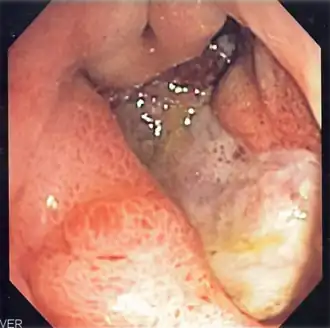

La esofagogastroduodenoscopia (EGD), también llamada endoscopia gastrointestinal alta, panendoscopia oral o simplemente gastroscopia (en algunos países hispanohablantes, las palabras terminadas en -scopia se usan con acento:-scopía) es un examen médico que visualiza el esófago, el estómago y el duodeno. Para su realización se utiliza un endoscopio, unos tubos flexibles cuya cabeza es móvil y controlada por el operador, en cuya punta tienen una cámara de video y una luz que ilumina el órgano examinado. La imagen es transmitida a un monitor en donde se pueden identificar lesiones como úlceras, erosiones y neoplasias de los órganos examinados. Durante el procedimiento también se pueden obtener muestras de tejido para realizar biopsias.

El examen también se puede emplear para obtener una muestra de tejido para realizar una biopsia. En una EGD, normalmente el esófago, el estómago y el duodeno deben estar lisos y de color carnoso. No debe haber sangrado, neoplasias, úlceras ni inflamación. Los resultados anormales pueden mostrar divertículos (bolsas anormales en el revestimiento de los intestinos), anillos esofágicos, esofagitis, estrechez de esófago, varices esofágicas, hernia de hiato, masas gástricas, inflamación del estómago y el duodeno, síndrome de Mallory-Weiss (desgarro), oclusión del tracto digestivo, tumores y úlceras (agudas o crónicas) en cualquiera de los tres órganos.

El endoscopista, con el paciente tumbado sobre su costado izquierdo, introduce el endoscopio por la boca en el esófago y luego procede a entrar al intestino delgado en su primera parte llamada duodeno. Desde allí se regresa examinando cada parte con detenimiento para encontrar lesiones. Si se encuentra una lesión se puede tomar una biopsia por el canal de trabajo del endoscopio.